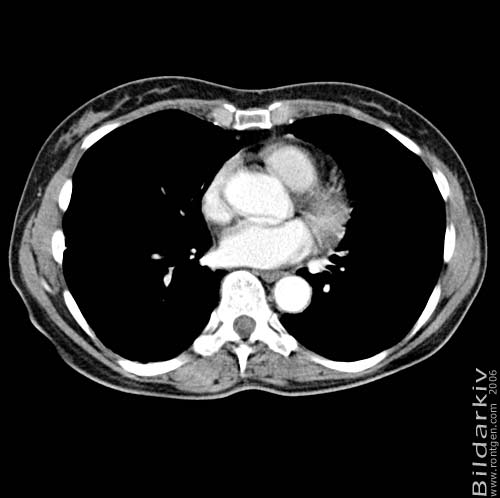

Thorax 35

Snitt över thorax med kontrast. Sk. mediastinum-fönstersättning.

CT Röntgen Helsingborgs lasarett

Mediastinum